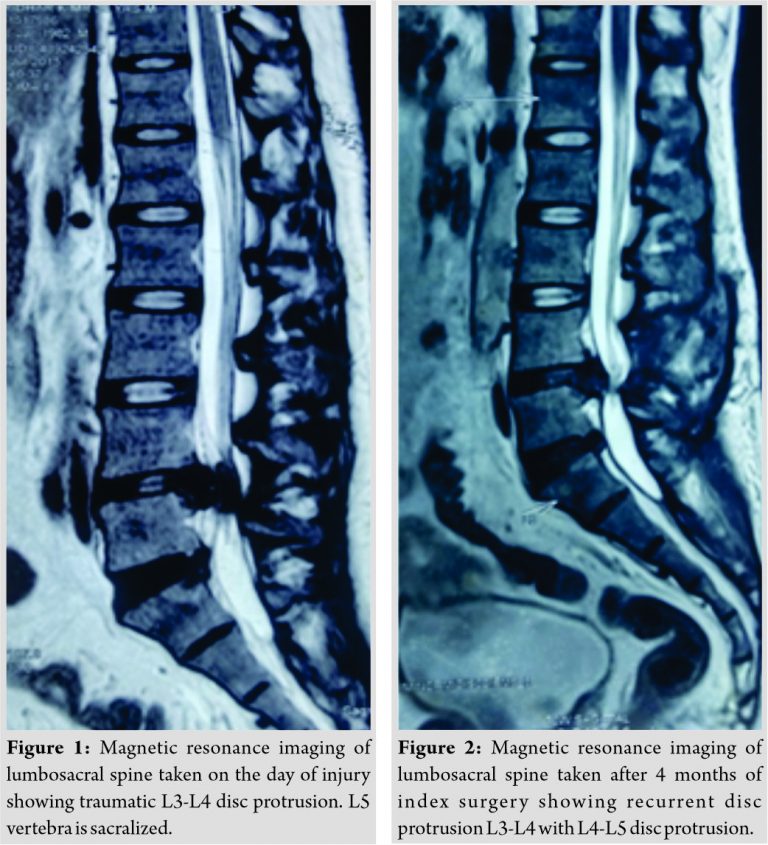

A 33-year-old gentleman came to our emergency department with a history of accidental fall from a ladder of about 10 feet height. Clinically, the patient had motor weakness in L4, L5, and S1 myotomes on the left side. There was no sensory deficit. Magnetic resonance imaging (MRI) revealed traumatic L3-L4 disc protrusion (Fig. 1). On the next day itself, L3 laminectomy with L3-L4 discectomy was done. The patient was discharged on the 5th post-operative day (POD) and was advised periodical follow-up. However, the patient did not review for a period of 4 months. At the end of 4 months, he presented with back pain and bilateral foot drop (L>R). MRI (Fig. 2) revealed recurrence of disc protrusion at L3-L4 level along with L4-L5 disc protrusion.